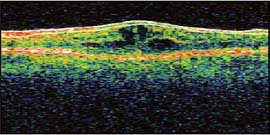

The patient was treated with prednisolone acetate and ketorolac tromethamine 0.4% (Acular LS, Allergan) q.i.d. He returned in 4 weeks, at which time his vision had improved to 20/25. He was instructed to taper his medications. However, he discontinued them on his own when he felt that his vision had recovered to its baseline. Three weeks later, the patient returned emergently, as the CME had recurred and his vision had decreased to 20/60. He was placed again on 1% prednisolone and ketorolac 0.4% q.i.d., returning 4 weeks later showing no evidence of CME on OCT, with 20/20 visual acuity (VA).

Figure 2. Normal macular anatomy showing the healthy foveal concavity and no evidence of edema or cystic changes (normal).